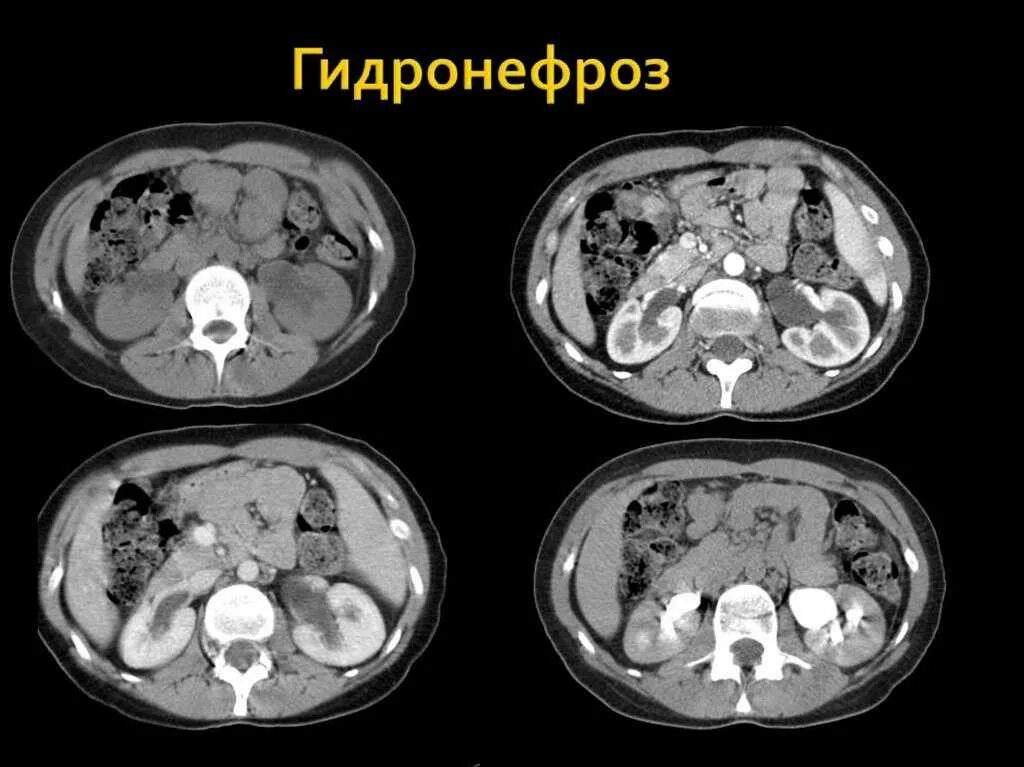

Пиелонефрит кт